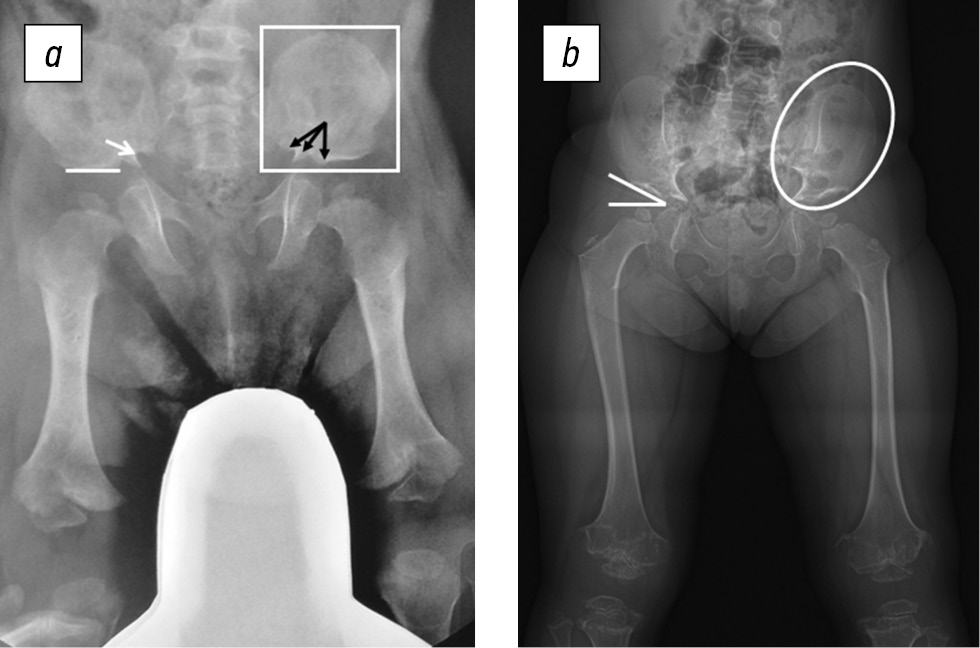

Характерные признаки на рентгенограммах, позволяющие проводить подтверждающую диагностику АХ у детей раннего возраста, включали квадратную форму крыльев подвздошной кости, плоскую горизонтальную вертлужную впадину, узкую седалищную вырезку, сужение междужкового расстояния в поясничном отделе позвоночника, короткие трубчатые кости с умеренным метафизарным расширением, рентгенопрозрачность проксимального отдела бедренной кости, брахидактилию с рентгенологической картиной симптома трезубца (рис. 4). В основе этого рентгенологического симптома лежит особенность оссификации надацетабулярной области, в результатом чего формируются «зубцы». Три «зубца», образованных кортикальным слоем седалищной вырезки, контурами оссифицированной части подвздошной кости и сводом вертлужной впадины, видны на рентгенограммах.

Рис. 4. Рентгенограммы тазобедренных суставов и бедренных костей в прямой проекции пациентов с ахондроплазией (а) и псевдоахондроплазией (б): а — горизонтальное положение свода вертлужной впадины (белая линия), суженная седалищная вырезка (белая стрелка), симптом трезубца (черные стрелки), квадратные очертания крыльев подвздошных костей (белый контур); б — скошенность свода вертлужной впадины (белые линии), овальные очертания крыльев подвздошных костей (белый контур)

Тазобедренные суставы | Квадратная форма крыльев подвздошных костей; горизонтальная вертлужная впадина и узкие седалищные вырезки, рентгенопрозрачность проксимального отдела бедра в младенческом возрасте; симптом трезубца | Маленькие круглые с нечеткими контурами эпифизы бедренной кости у детей; неравномерная оссификация свода вертлужной впадины; выраженный диспластический коксартроз у взрослых |